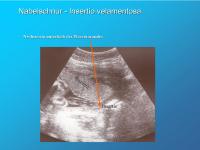

Nabelschnur - Insertion velamentosa

Abbildung 5

Keywords: Insertio velamentosaNabelschnuransatz